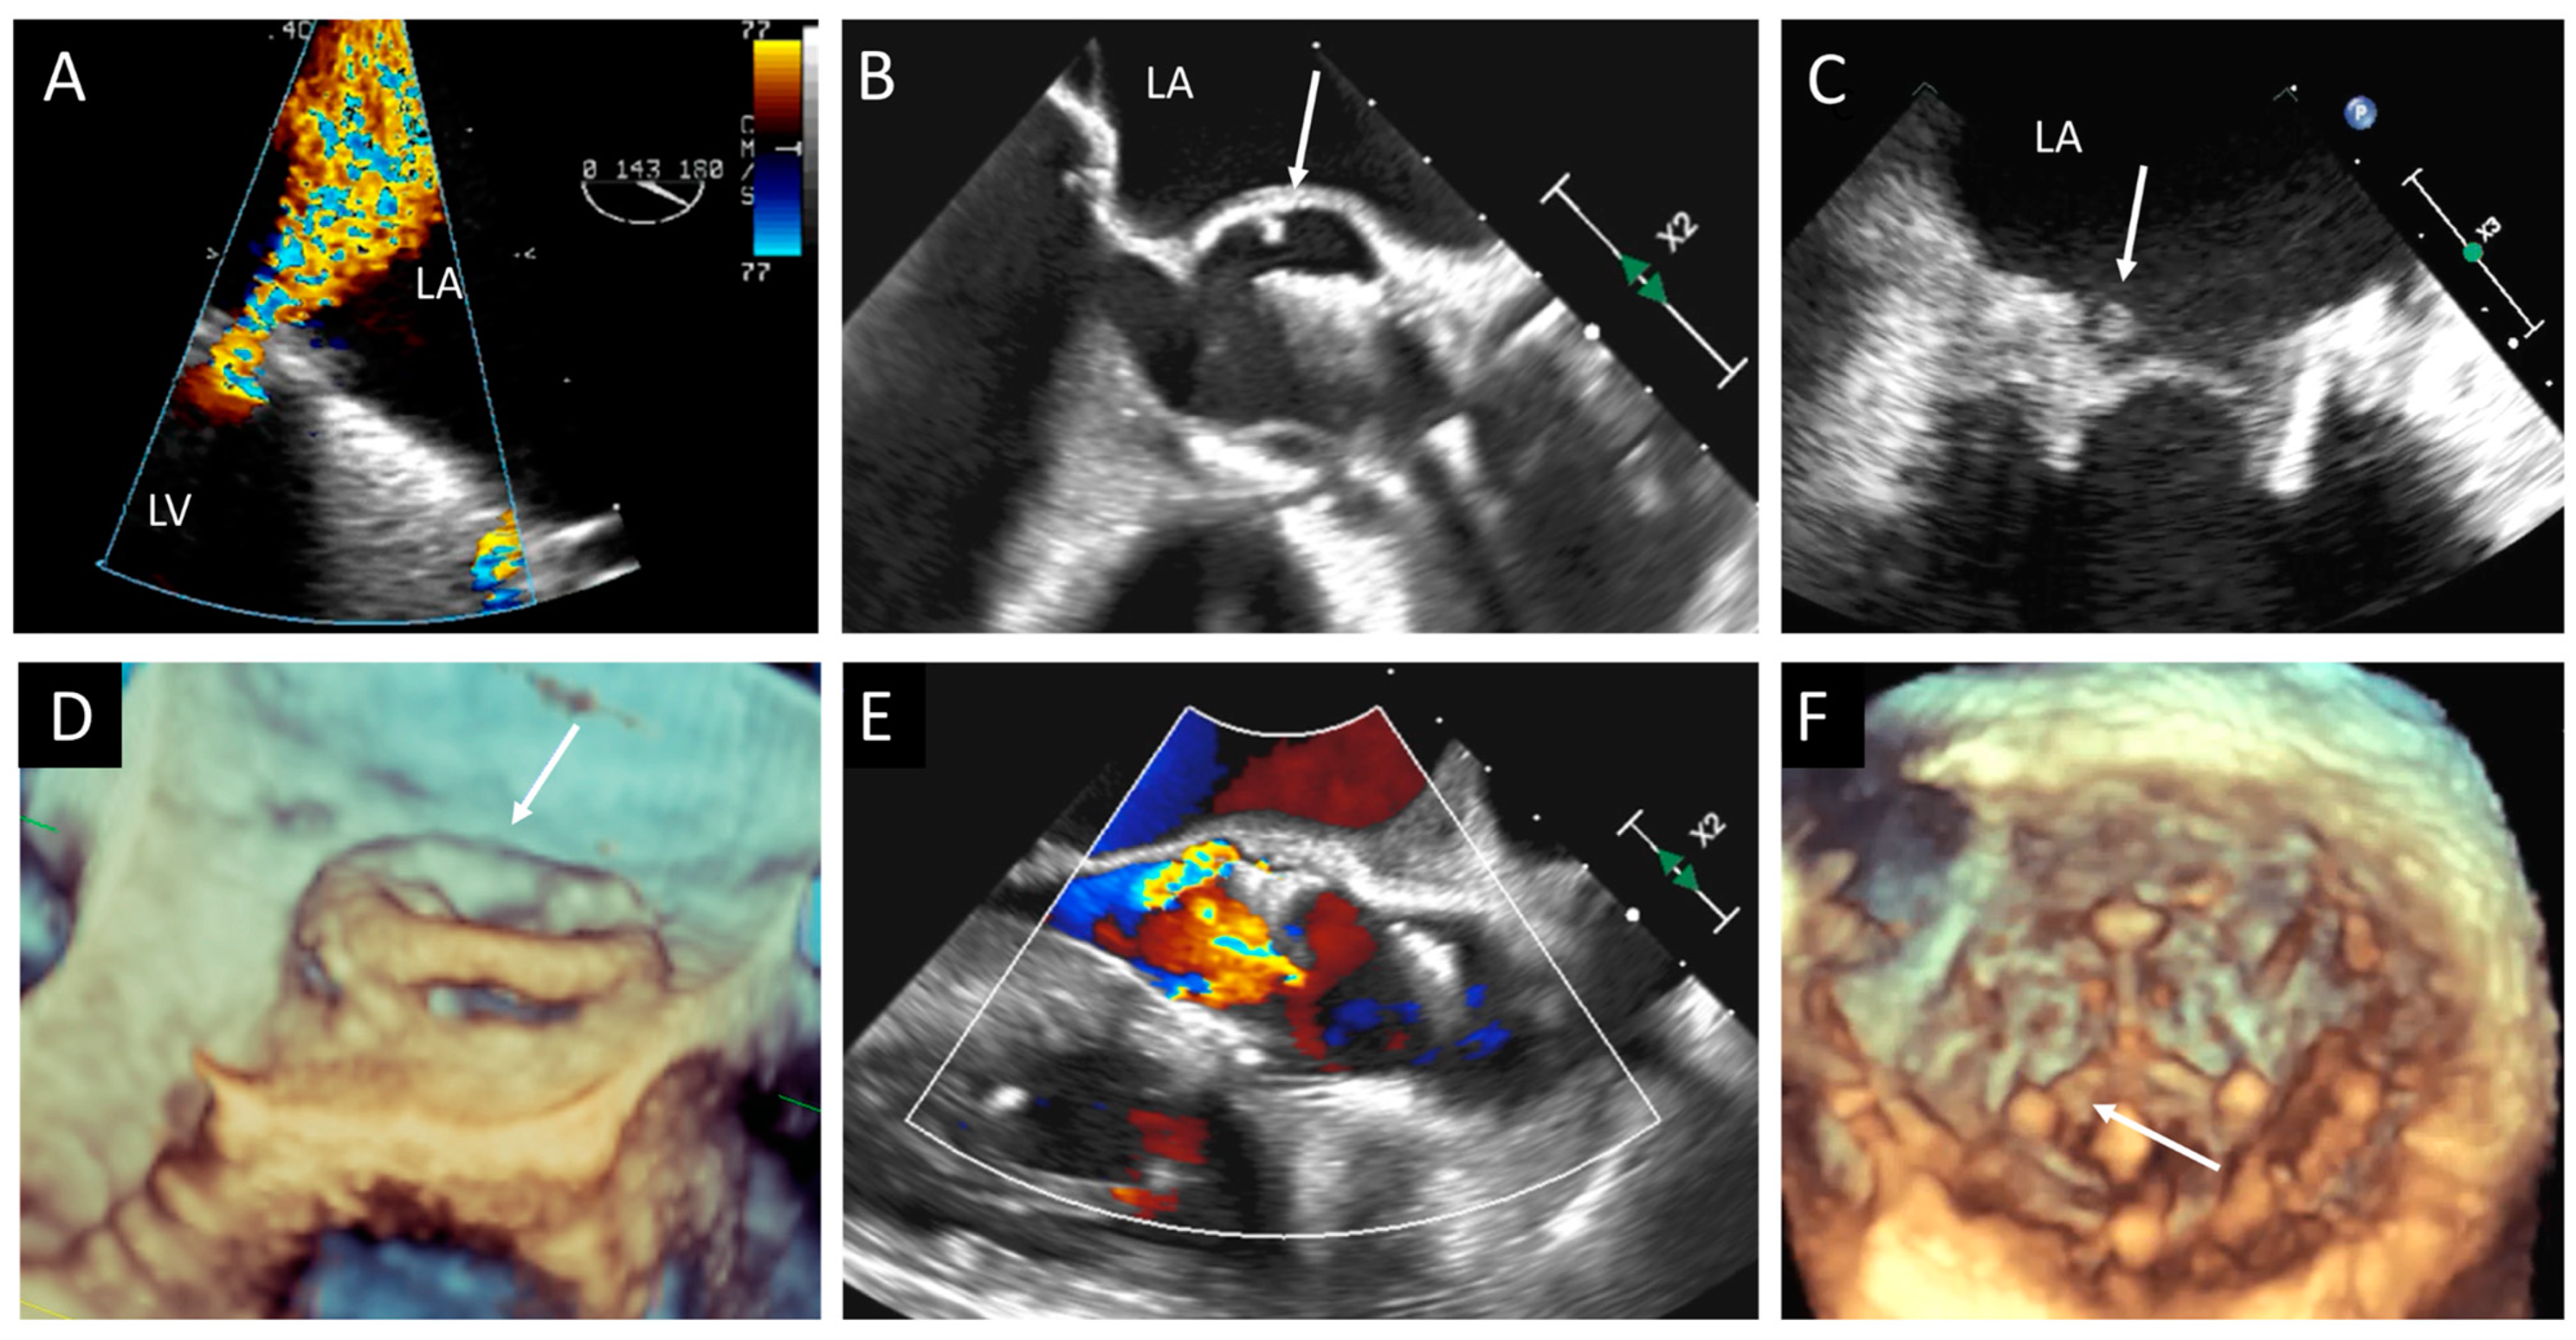

Figure 7. Three cases of prosthetic valve endocarditis: (A,D) dehiscence and para-prosthetic leak of a mitral valve prosthesis (arrow), (B,E) pseudoaneurysm (arrow) of an aortic prosthesis, and (C,F) small vegetation (arrow) in a prosthetic MV visualized in 2D TEE and confirmed in 3D TEE from LV view. LA, left atrium; LV, left ventricle; MV, mitral valve; TEE, transesophageal echocardiography.